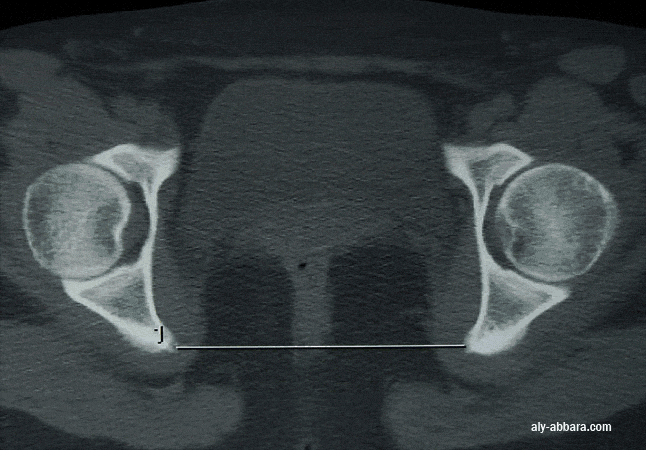

" le détroit moyen et le diamètre bi-épineux ou bi-sciatique "

Diamètre bisciatique (ou bi-épineux) Diamètre bi-épineux: c'est la distance séparant les deux épines sciatiques.

En moyenne, il mesure

100 à 105 mm.